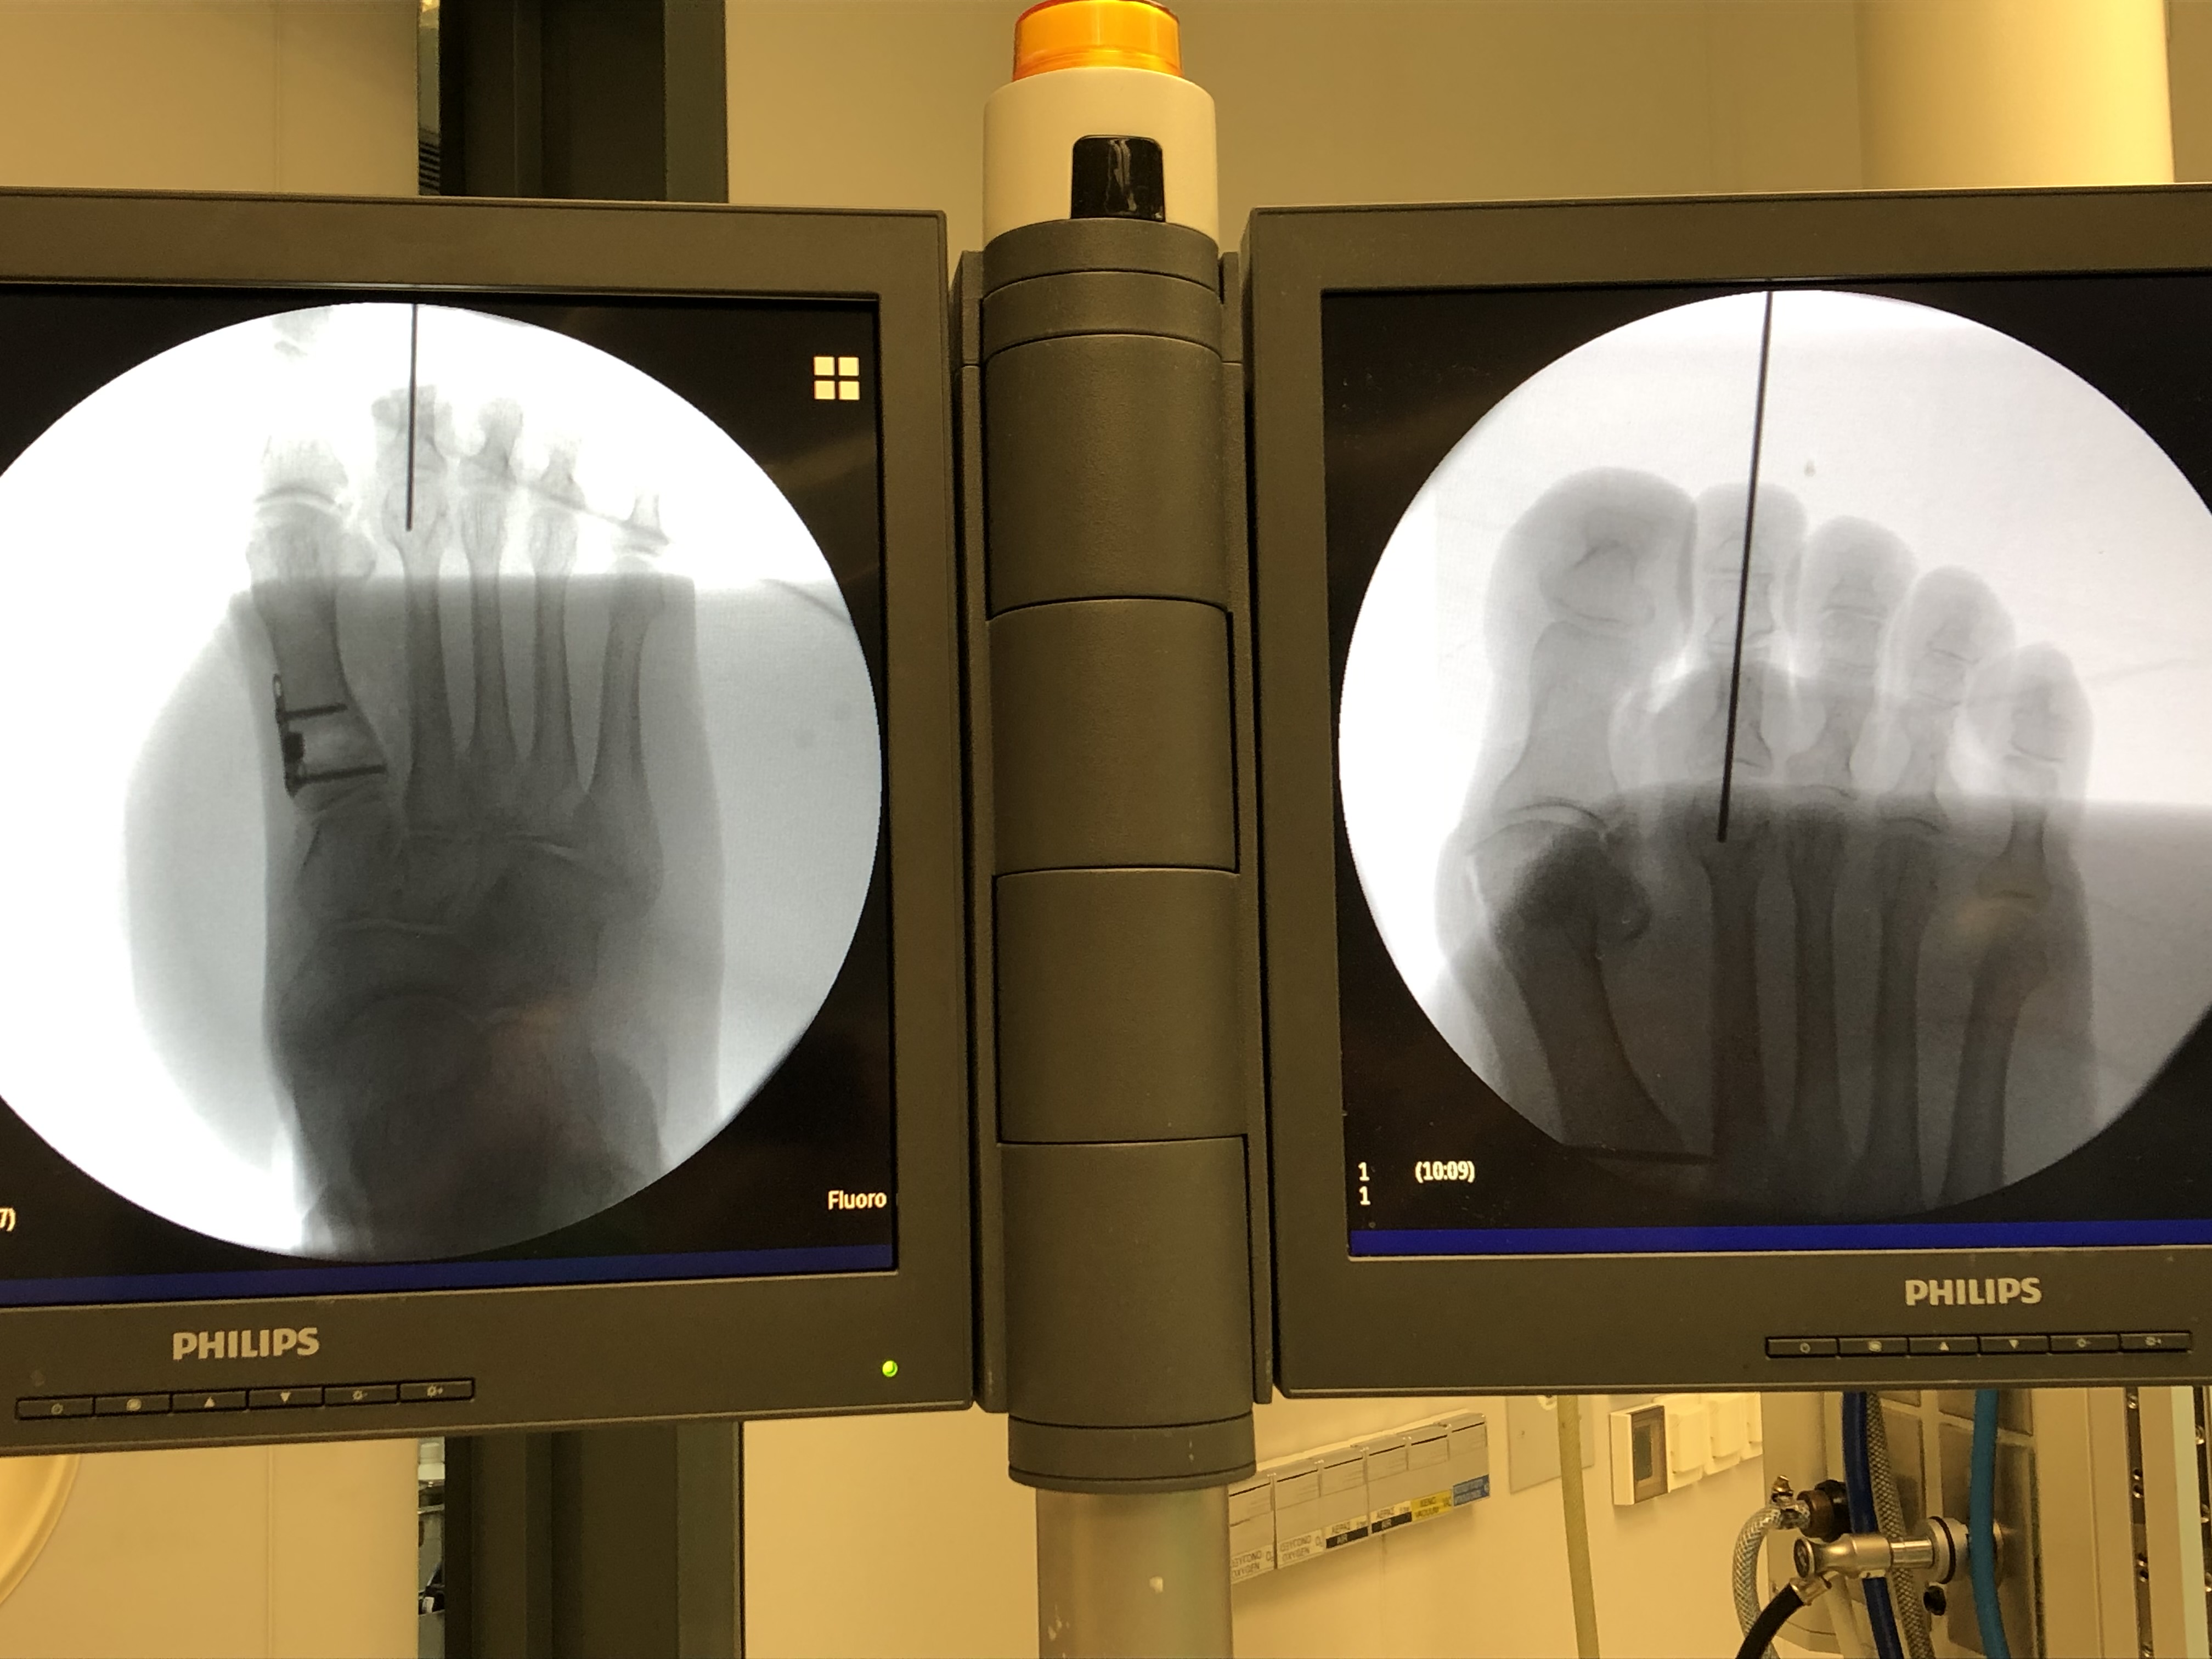

Επεμβάσεις ελάχιστης επεμβατικότητας, όπως είναι για παράδειγμα η διαδερμική τεχνική, μπορεί να χρησιμοποιηθεί για την αντιμετώπιση βλαισού μέγα δακτύλου στις πιο ήπιες παραμορφώσεις.

Οι επεμβάσεις πραγματοποιούνται με γενική ή περιοχική αναισθησία και ο ασθενήςείναι σε θέση να περπατήσει την ίδια ημέρα με τη χρήση κατάλληλων υποδημάτων χωρίς κάποιο επιπλέον βοήθημα. Σταδιακά επιστρέφει στις καθημερινές του δραστηριότητες, απαλλαγμένος πλήρως από τα συμπτώματα.